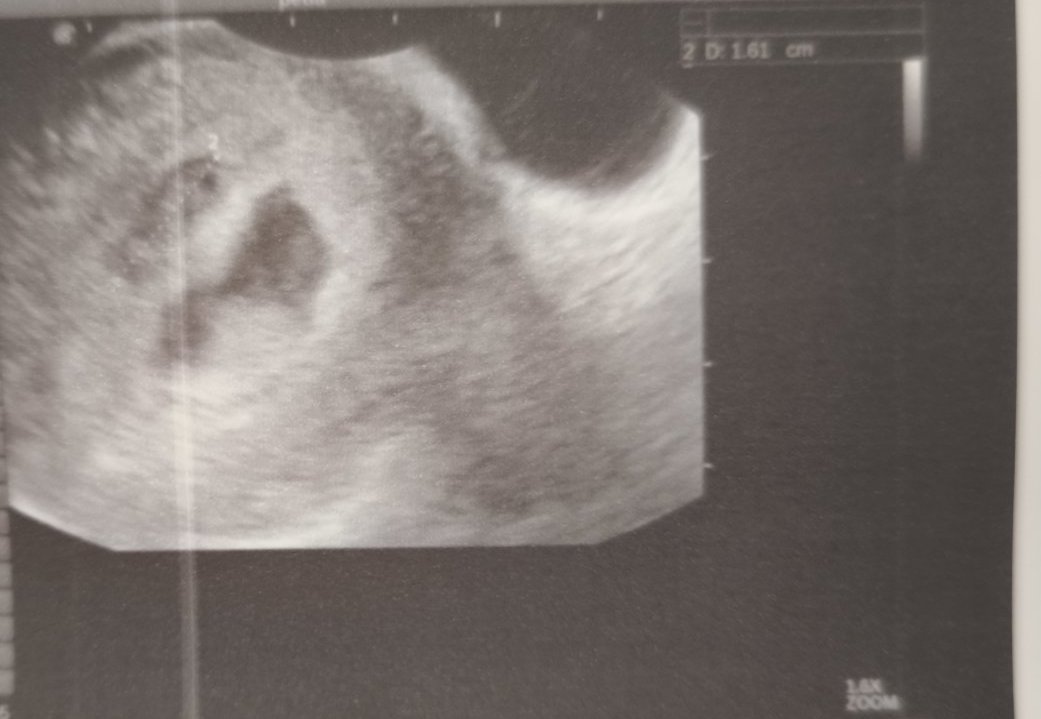

Оказа се, че има отлепване и то доста голямо, около 2 см. Ембрионът е жив, има сърдечна дейност. Изписаха ми утрогестан 2*2 , но шпа 3*2, вит. Ц , спирам аспирина и го заменям с вит. К.  и да пазя леглото.

Над 1 см е, близо 2...

16 мм го е записал в амбулаторния лист.

На последния преглед беше 9.8 см във вторник, но сега не ми каза и не го е записал. Само каза, че е по-голям от отлепването. Аз бях прекалено разревана, за да се сетя да питам (яко ме е ударил хормона, по принцип не съм ревлива 😃) Прикачвам двете снимки от ехографа. Май е записал, че ембриона е 0. 28 см